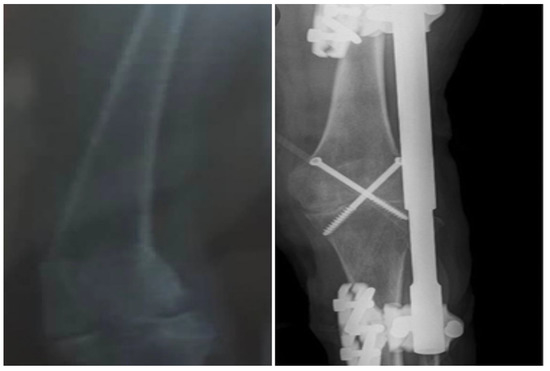

The initial therapeutic approach was a percutaneous crossed pins application (Figure 2).

Figure 2. Plain X-ray of the left knee with percutaneous cross-pins for bone stabilization.